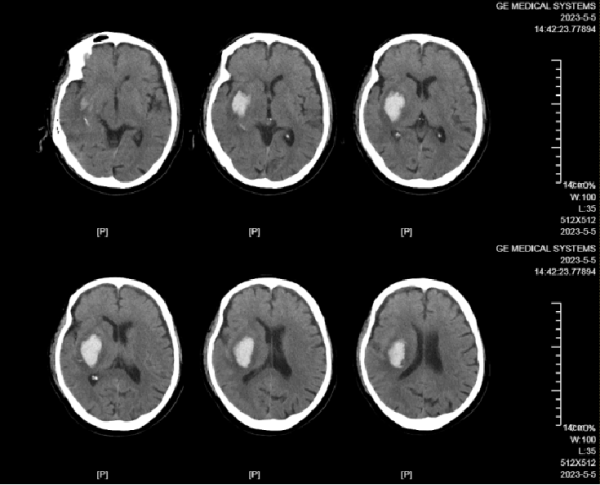

70岁的患者张大爷因“突发左侧肢体活动障碍20小时”被紧急送入医院。经过详细的检查,发现他的头部CT结果显示右侧壳核出血,颅内血肿压迫了内囊结构,导致了左侧上肢肌力2级,下肢肌力4级的肢体活动障碍。

术后复查CT显示,引流管位置理想——位于血肿中心,贯穿血肿长轴。理想的置管位置,是血肿尽快、充分引流的关键,也降低了术中穿刺和术后引流过程中血肿周边脑组织的副损伤。

术后尿激酶注射1次,于术后1天复查头部CT(左图),血肿绝大部分被引出,拔除引流管(右图)。理想的血肿引流效果,是在功能恢复的基础上,用更短的引流管留置时间,大大降低了术后感染风险。